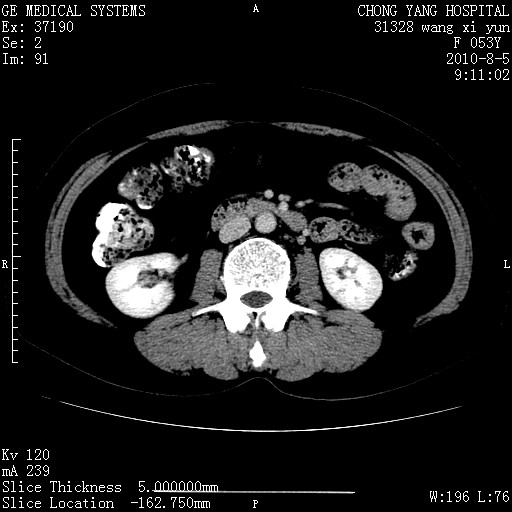

标题: CT28214:F41Y 血尿二十天,建议盆腔平扫加增强。

1)考虑肝左叶胆管细胞癌。2)脂肪肝。